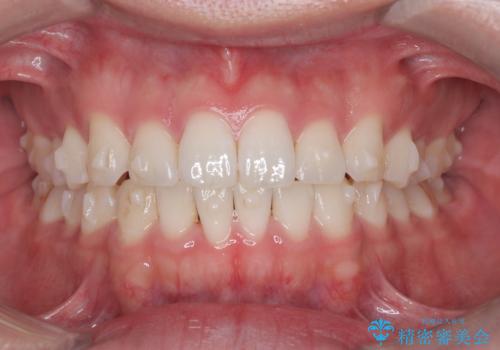

歯のデコボコを治したい|インビザラインで綺麗な歯並びに!|矯正期間は6ヵ月!

- 歯のデコボコが気になるを主訴に来院された患者様です。

インビザラインで歯は抜かずに非抜歯でデコボコを改善しました。

インビザラインで叢生の改善を行いました。

歯は抜かずに、拡大と少しのIPRで並べました。

矯正期間は半年です。

綺麗な歯並びを手に入れ大変ご満足していただきました。